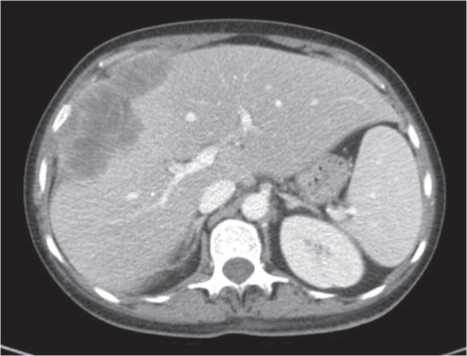

Через 6 мес от начала терапии при контрольном обследовании на КТ с контрастированием было зарегистрировано уменьшение суммы таргетных очагов до 184 мм (-9% от исходной), что соответствует стабилизации по критериям mRECIST (рис. 5, 6).

Рис. 6. КТ ОБП через 6 мес от начала терапии ленватинибом, венозная фаза. Сумма наибольших диаметров таргетных очагов 184 мм.

Fig. 6. Venous phase abdominal CT scans 6 months after starting lenvatinib therapy. The sum of the longest diameter of the target lesions is 184 mm.